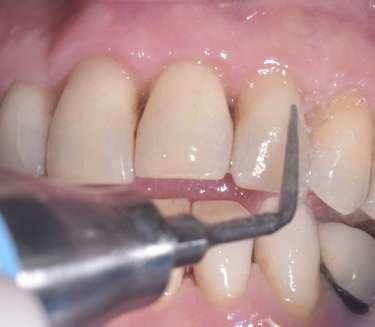

L'evoluzione dell'ozonoterapia professionale si avvale del Trolley Komby Dental Ozone Active (GEMAVIP), un apparecchio professionale che utilizza un generatore medicale di ozono per trasformare l’ossigeno fornito da ossigenatore (93% purezza) in ozono, e quindi per ozonizzare l’acqua bidistillata posta in una ampolla di vetro pirex da 3 lt. La saturazione dell’acqua avviene dopo 15 minuti pari a circa 20ugr/ml disciolti. L’apparecchio elettronico è automatico, con tutte le funzioni operative poste su touch screen.

L’acqua ozonizzata prodotta da questo medical device potrà essere inserita nei contenitori degli ablatori in modo da eseguire un debridement parodontale potenziato dalle proprietà battericida dell’ozono durante il trattamento parodontale non chirugico.

L’uso dell’acqua ozonizzata dal Trolley Komby Dental Ozone Active permetterà durante i trattamenti odontoiatrici di avere tutti i vantaggi clinici descritti in letteratura dall’ozonoterapia e quindi contrastare l’infiammazione dei tessuti parodontali e implantari ed accelerare i processi di guarigione. Incoming ulteriori evidenze scientifiche. L'ATASIO ha programmato

una serie di eventi dedicati all'ozonoterapia domiciliare e professionale alla luce dell'evoluzione dei protocolli operativi con utilizzo di questa significativa tecnologia.

stare inquinamento da batteri e virus. L’igienizzazione degli allineatori invisibili e degli apparecchi ortodontici mobili con ergonomici spray all’olio di oliva ozonizzato Ialozon clean (Gemavip) permette di mantenere la trasparenza del dispositivo ortodontico invisibile ed un più facile utilizzo nella fascia d’età adolescenziale. Al termine della terapia è fondamentale dopo il debonding, eseguire un clean-up ortodontico attento. Il Clean Up è l'innovativo approccio clinico che, grazie all’ausilio degli ultrasuoni e dell’inserto piezoelettrico D05120 con diamantatura D30 e dell’inserto D07102 con parte operativa in PEEK D06007 (MECTRON) permette la rimozione minimamente invasiva dei residui di adesivi e/o compositi a seguito di terapia ortodontica standard o invisibile. Il nuovo protocollo ENAMEL SAFE POST DEBONDING (G. M. Nardi et al.) “SMALTO SICURO POST DEBONDING” con tecnologia piezoelettrica si è dimostrato efficace e sicuro per il clean-up ortodontico. (Enamel Analysis by 3D Scanning after Three Orthodontic Clean- Up Procedures: An In-Vitro Test of a New Piezoelectric Tool).